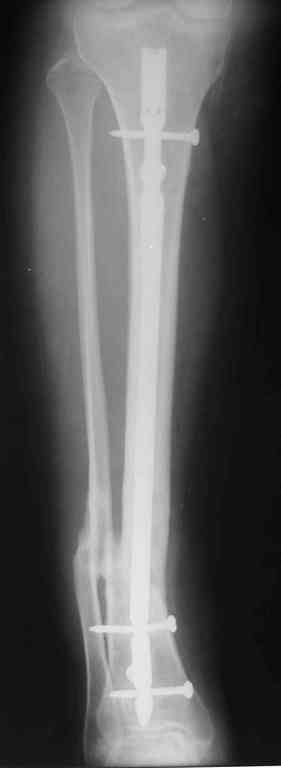

Прилагаются.

Да , обсуждалась и оптимальным штифтом был выбран " Мастер" Остеомед 10 мм и винты 5 мм, но увы все наши благие намерения разбились о нашу действительность и материальные возможности больной, обращение ее в страховую компанию и т.д., вообщем выкручивались из внутренних резервов, а они были такими 9 мм штифт Остеомед, под 4 мм винты. Ограничили нагрузку. Ошиблись еще и с оценкой сращения, дали полную нагрузку+ больная поправилась на 18 кг, и вот теперь имеем , что имеем.

Действитльность и возвожности остались прежнее, во внутренних резервах есть 11 мм стержень универсальный ( реконструктивный) "Деост-CHM" много спиц и аппарат + ось конечности и отломок штифта и надежда на Ваши советы.